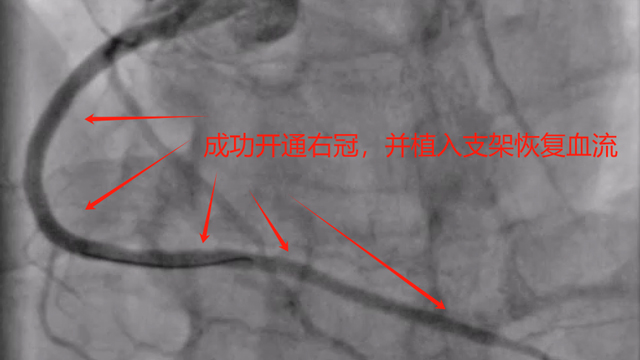

近期,来凤县人民医院心血管内科成功为多支冠脉慢性完全闭塞(CTO)患者开通右冠闭塞血管,同时在冠脉血管内超声(IVUS)指导下,成功植入支架恢复闭塞血管血流,标志着该院冠脉介入水平再上新台阶。〔全文〕